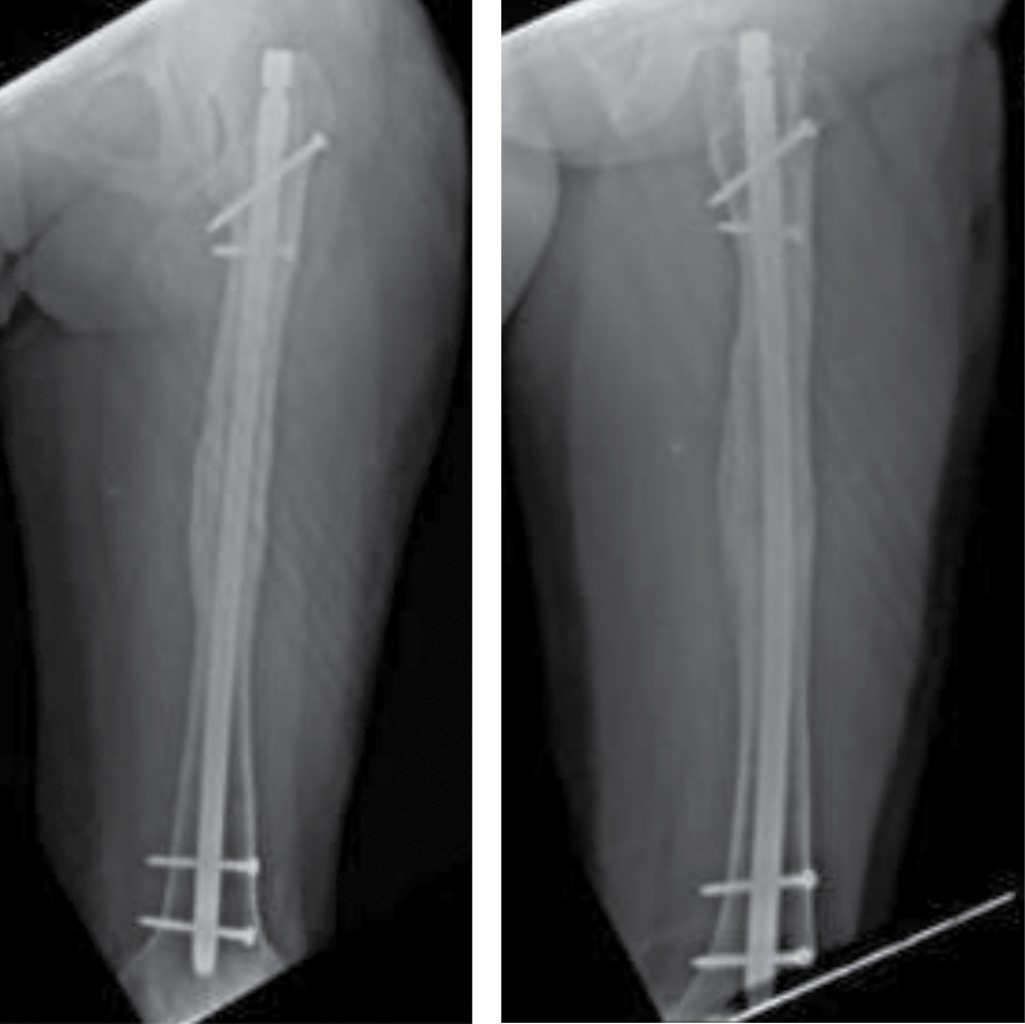

Pseudoarthrosis is a complication that poses a challenge for the orthopedist. If is associated with bone loss, a salvage surgery is indicated. There is no protocol for treatment for pseudoarthrosis with a "critical defect". The induced membrane technique, distraction osteogenesis, among others, has been described; however, the long time and elevated costs involved have opened a new landscape on the research of new protocols. The "diamond concept" which is not only based of improving biomechanics, but also introduces biological stimulation as a pillar of treatment, was recently introduced. We present the case of a 16-year-old female patient with a femoral shaft fracture after a traffic accident, treated initially with a centromedullar blocked nailing that progresses to pseudoarthrosis, presenting a 5 cm bone loss. Treatment consisted of removing the centromedullar blocked nail, resection of the nonviable bone segment, osteosynthesis with another centromedullar blocked nailing, placement a 7 cm diaphyseal allograft, platelet-rich plasma (PRP), matrix allograft, and bone chips, thus achieving radiographic and clinical consolidation; restoring limb function in a shorter time, considering the PRP as the main orthobiological element in this case.

Figure 1